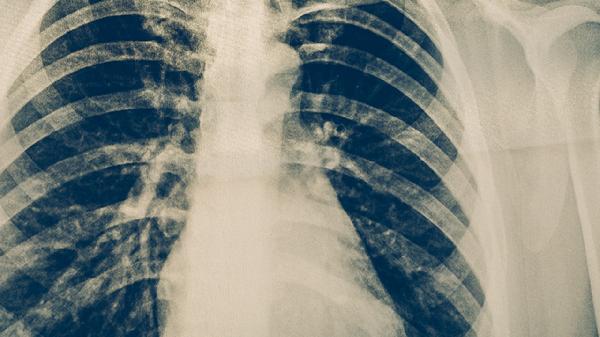

服用抗结核药物后皮肤变黑属于药物不良反应,可能与异烟肼、利福平等药物引起的色素沉着有关。皮肤颜色改变通常在停药后逐渐恢复,但需警惕药物过敏或肝肾功能异常等严重反应。

抗结核药物导致皮肤色素沉着的机制复杂,异烟肼可能通过干扰酪氨酸代谢影响黑色素合成,利福平则可能与胆红素代谢异常相关。部分患者用药2-3个月后出现面部、手掌等暴露部位肤色加深,通常呈均匀分布且无瘙痒疼痛。这种改变具有剂量依赖性,联合用药时更易发生。临床观察发现皮肤色素沉着在深肤色人群中更明显,但不会影响药物疗效。

少数患者可能出现严重的过敏反应,表现为皮肤快速变黑伴随皮疹、发热或黏膜损伤,需立即停药处理。长期大剂量使用吡嗪酰胺时,可能诱发光敏反应导致暴露部位色素沉着加重。个别病例报告显示,乙胺丁醇可引起指甲床色素改变。对于合并HIV感染的结核病患者,抗逆转录病毒药物与抗结核药的相互作用可能加剧皮肤不良反应。

建议用药期间做好防晒措施,避免紫外线直射加重色素沉着。定期监测肝功能及皮肤变化,若出现皮肤变黑伴随黄疸、尿色加深等症状需及时就医。停药后色素沉着多数在3-6个月消退,顽固性病例可咨询皮肤科医生进行局部治疗。保持均衡饮食并补充维生素B族,有助于减轻药物对皮肤的影响。